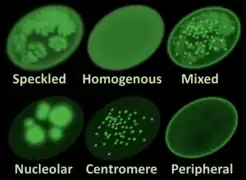

Indirect immunofluorescence is one of the most commonly used tests for ANAs. Typically, HEp-2 cells are used as a substrate to detect the antibodies in human serum. Microscope slides are coated with HEp-2 cells and the serum is incubated with the cells. If the said and targeted antibodies are present then they will bind to the antigens on the cells; in the case of ANAs, the antibodies will bind to the nucleus. These can be visualised by adding a fluorescent tagged (usually FITC or rhodopsin B) anti-human antibody that binds to the antibodies. The molecule will fluoresce when a specific wavelength of light shines on it, which can be seen under the microscope. Depending on the antibody present in the human serum and the localisation of the antigen in the cell, distinct patterns of fluorescence will be seen on the HEp-2 cells.[51][52] Levels of antibodies are analysed by performing dilutions on blood serum. An ANA test is considered positive if fluorescence is seen at a titre of 1:40/1:80. Higher titres are more clinically significant as low positives (≤1:160) are found in up to 20% of healthy individuals, especially the elderly. Only around 5% of the healthy population have ANA titres of 1:160 or higher.[8][53]

There are many nuclear staining patterns seen on HEp-2 cells: homogeneous, speckled, nucleolar, nuclear membranous, centromeric, nuclear dot and pleomorphic. The homogeneous pattern is seen when the condensed chromosomes and interphase chromatin stain. This pattern is associated with anti-dsDNA antibodies, antibodies to nucleosomal components, and anti-histone antibodies. There are two speckled patterns: fine and coarse. The fine speckled pattern has fine nuclear staining with unstained metaphase chromatin, which is associated with anti-Ro and anti-La antibodies. The coarse staining pattern has coarse granular nuclear staining, caused by anti-U1-RNP and anti-Sm antibodies. The nucleolar staining pattern is associated with many antibodies including anti-Scl-70, anti-PM-Scl, anti-fibrillarin and anti-Th/To. Nuclear membrane staining appears as a fluorescent ring around the cell nucleus and are produced by anti-gp210 and anti-p62 antibodies. The centromere pattern shows multiple nuclear dots in interphase and mitotic cells, corresponding to the number of chromosomes in the cell. Nuclear dot patterns show between 13 and 25 nuclear dots in interphase cells and are produced by anti-sp100 antibodies. Pleomorphic pattern is caused by antibodies to the proliferating cell nuclear antigen.[26][53][57][58] Indirect immunofluorescence has been shown to be slightly superior compared to ELISA in detection of ANA from HEp-2 cells.[54]